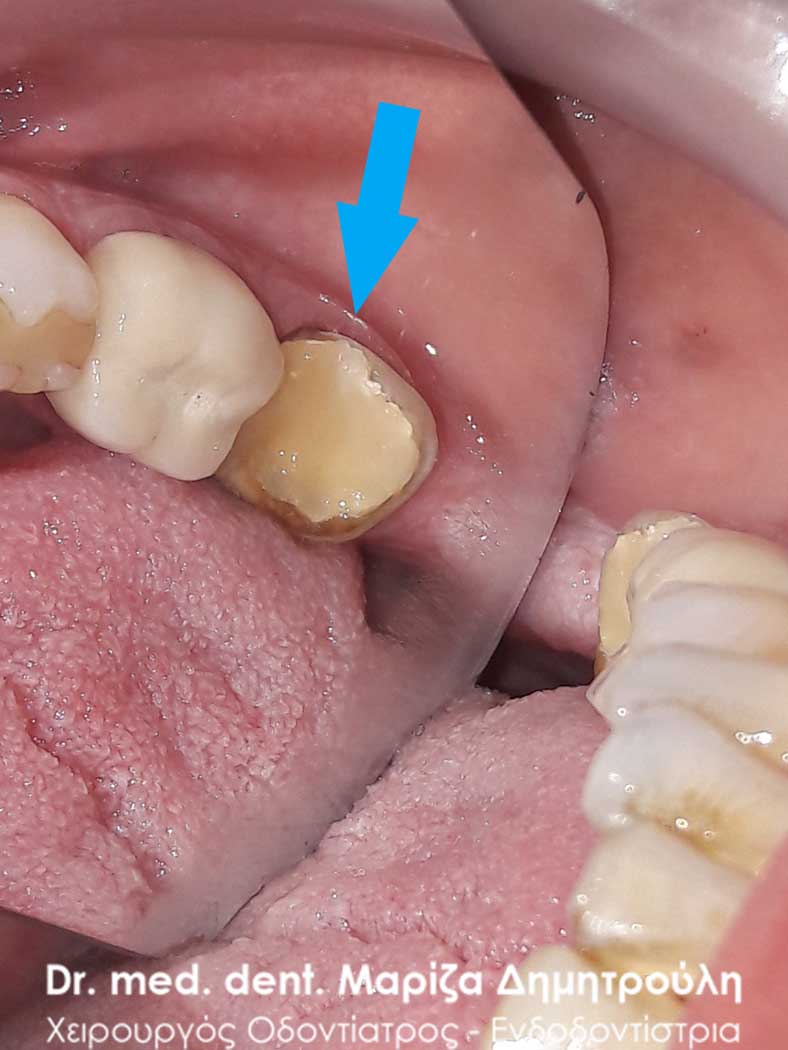

Αρχική κλινική εικόνα του παλιού σπασμένου σφραγίσματος

Εικόνα του δοντιού πριν τη λήψη αποτυπώματος